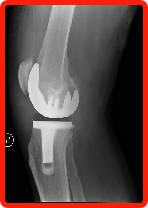

Bob Faught's anesthesia has been spinal/ epidural for his surgeries, especially total knee & hip replacements. He stays wide awake with no amnesia or sleeping medications. He will share some very interesting insights into total joint replacement: When you get in the operating room, most people are almost asleep. What you don't see is the extensive time & effort it takes the nursing staff to prepare the room for total joint replacement surgery. I have a great deal of respect the the nursing teams after what I have seen. After they place you on the operating table, they give you the spinal/ epidural that eventually numbs you from the waist down. The staff then insures all the IV connections are in place while they begin the preparation on your joint. For example, like in knee replacement, they need to shave your leg & clean it. Also, the anesthesiologist stays right with you by your head to make sure you are comfortable. The team then places the green "tent" around your joint to protect everyone from the procedure & help prevent any possible infections. After the spinal/ epidural has taken full effect, the doctor & his/ her team begin the joint replacement. After they make the necessary cuts through your skin to the joint, they remove the diseased joint. From the x-rays, they know about what size joint you will need & have this size range available in the operating room. To determine the exact size, they use color-coded plastic prosthesis parts, put them in to simulate your new joint, and check for final fit. Once they have concluded what size fits best, many times the joint manufacturer's rep is in the operating room & opens the sealed envelope with your new joint. This service is important for multiple reasons: insure the correct size and position, right or left, for example, is given to the doctor. It also insures that the manufacturer was there to open the bacteria-free prosthesis & hand it to the doctor for maximum protection. The doctor places the new prosthesis in & goes through a final inspection. Then the doctor uses staples to close up the incision used to replace your joint. From that point on, the anesthesiologist makes sure you are still comfortable, and the nurses begin the clean-up. They then bring in another gurney to take you to the recovery room for about an hour to 1-1/2 hours till all vital signs are good & you are ready to be taken to your room. |